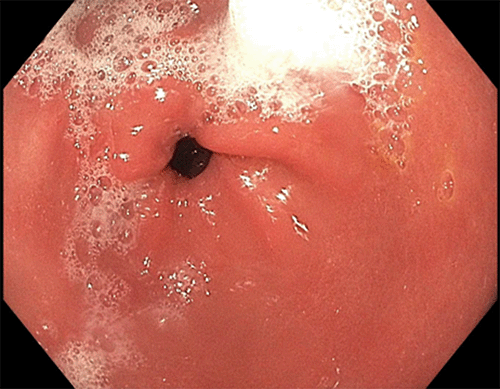

In the first case, the patient, a 37-year-old Caucasian male, presented with a one-year history of intermittent left upper quadrant abdominal pain. His past medical and surgical history was significant for obesity (BMI 39 kg/m2), hypertension, hyperlipidemia, Hashimoto’s thyroiditis, and inguinal hernia repair. He had a history of prolonged NSAID use but no history of smoking or significant alcohol consumption. His symptoms transiently improved with proton pump inhibitors (PPI) and antacids. He had a family history of gastric and colonic polyps in his father and bladder cancer in his paternal aunt. He had no family history of gastric cancer. Based on his symptoms, he was referred to gastroenterology. He underwent an esophagogastroduodenoscopy (EGD) that revealed multiple gastric polyps in the fundus and body of the stomach with antral sparing (Figure 1 and Figure 2), no polyps in the duodenum, and Los Angeles grade A reflux esophagitis. Biopsies were obtained and returned as fundic gland polyps without evidence of dysplasia on pathology. He underwent a colonoscopy that revealed small internal hemorrhoids and diverticula. No polyps were identified. His serum gastrin level was normal. The patient was referred for genetic counseling and testing and was found to have the c.-191T>C mutation in the APC promoter region seen in the setting of GAPPS. The patient had no known history of familial cancer syndrome. He had no evidence of metastatic disease on CT of the abdomen and pelvis.

Figure 2. Prepyloric Stomach—Pathognomonic Feature of Antral Sparing. Published with Permission